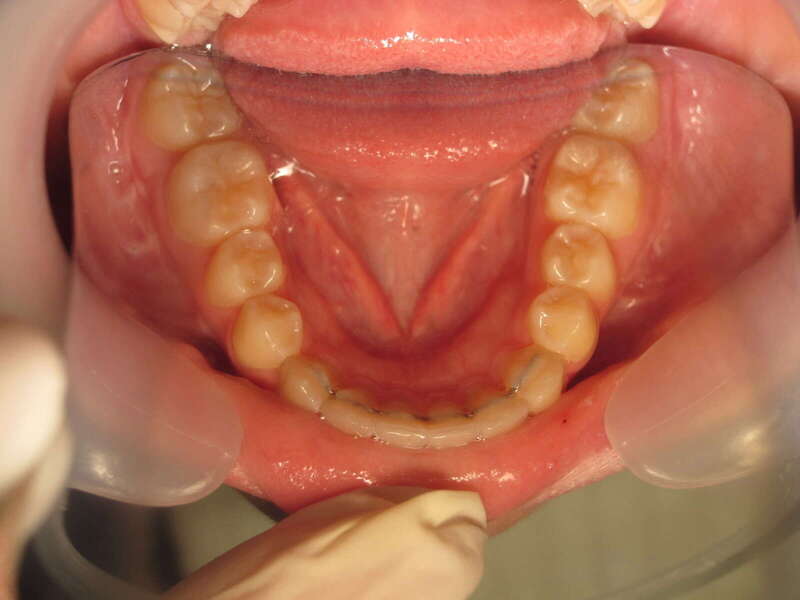

Cas n°9 traité par multi-attaches - adolescent

Ce cas d'adolescent illustre une stratégie de développement d'arcade réussie. Le patient présentait un encombrement massif et des inversions d'articulé rendant l'occlusion instable.

Le traitement a été réalisé avec des multibagues autoligaturantes, choisies pour leur capacité à générer des forces légères et continues, idéales pour l'expansion transversale. Cette approche a permis de corriger l'encombrement et les inversions d'articulé sans extractions dentaires, en remodelant simplement la forme des arcades.

Résultats clés :

• Transformation d'arcade : Passage d'une arcade étroite et encombrée à une arcade large et fonctionnelle.

• Occlusion optimale : Rétablissement d'un engrènement sain, protégeant les dents contre les usures anormales.

• Esthétique naturelle : Le sourire est élargi, harmonieux et parfaitement intégré au profil du patient.

C'est une démonstration de l'efficacité biologique de l'orthodontie moderne, qui privilégie la conservation dentaire et le respect des structures osseuses.